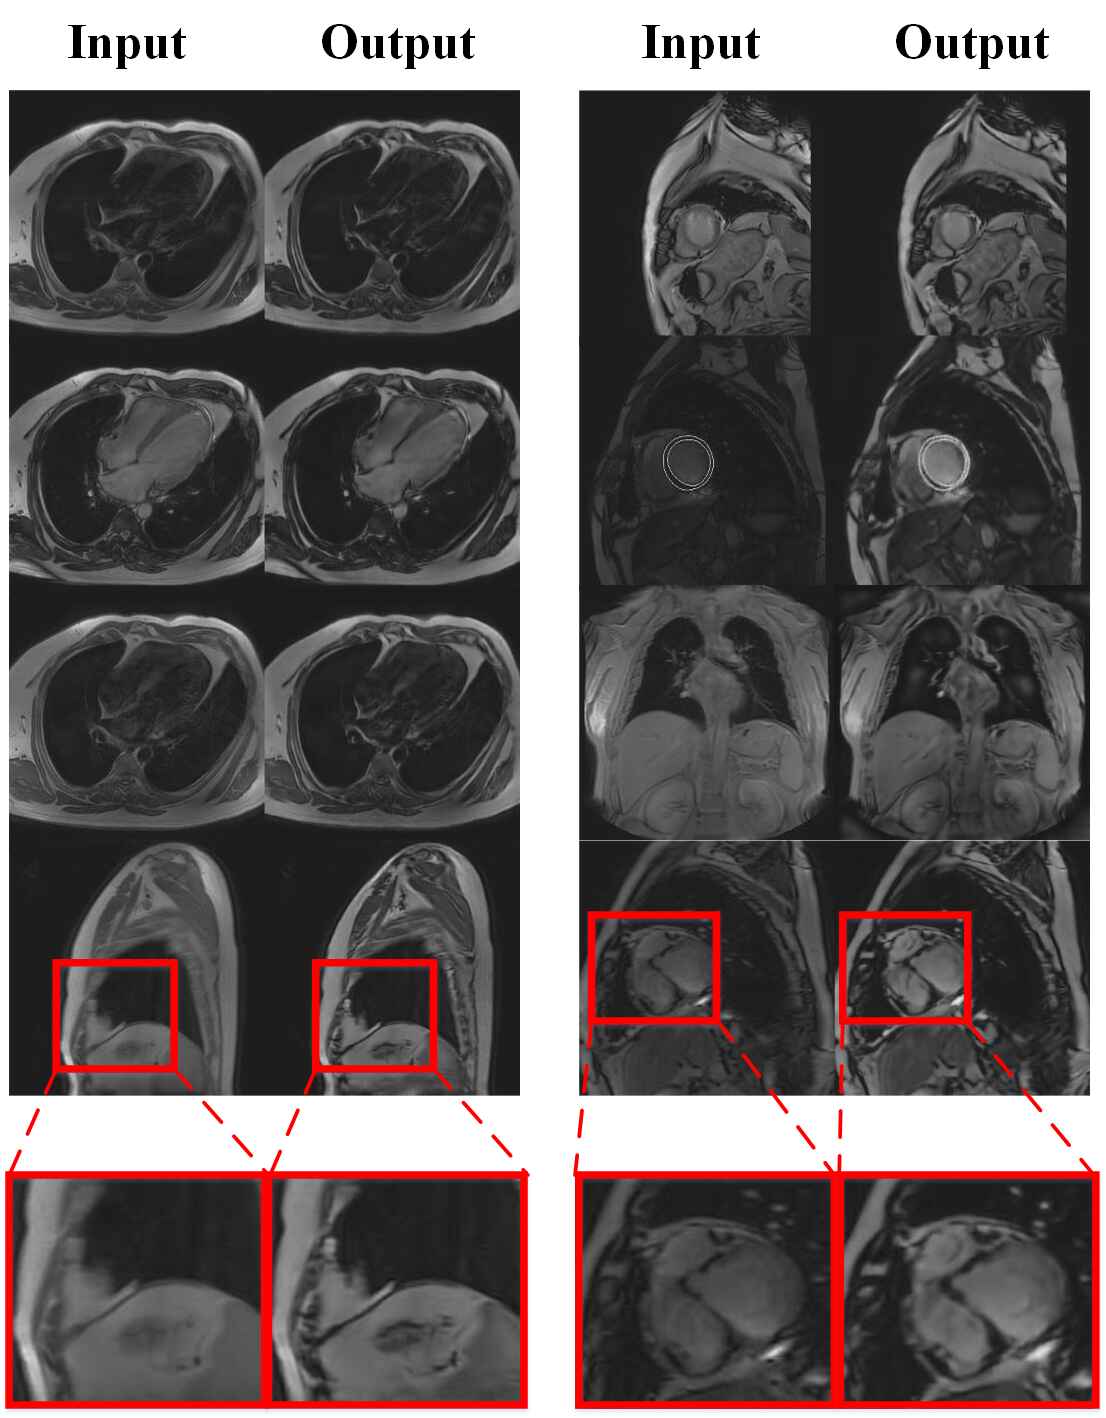

Results of motion artifact correction on example scans from our four Motion Artifact Correction deep learning has been introduced for reducing motion artifacts without the need for supplementary data acquisition (6, 31,. motion artifacts are a frequent source of image degradation in the clinical. relying on user inputs for motion detection introduces subjectivity into the detection of motion artifacts. motion correction visually and quantitatively improves the image quality of real. Motion Artifact Correction.

Motion artifact correction results of liver data with real motion Motion Artifact Correction motion artifacts are a frequent source of image degradation in the clinical. motion correction visually and quantitatively improves the image quality of real motion artifact affected data. in this study, we proposed wcbsi as a new approach to motion correction in fnirs signals, which combines two existing ma correction. relying on user inputs for motion detection. Motion Artifact Correction.